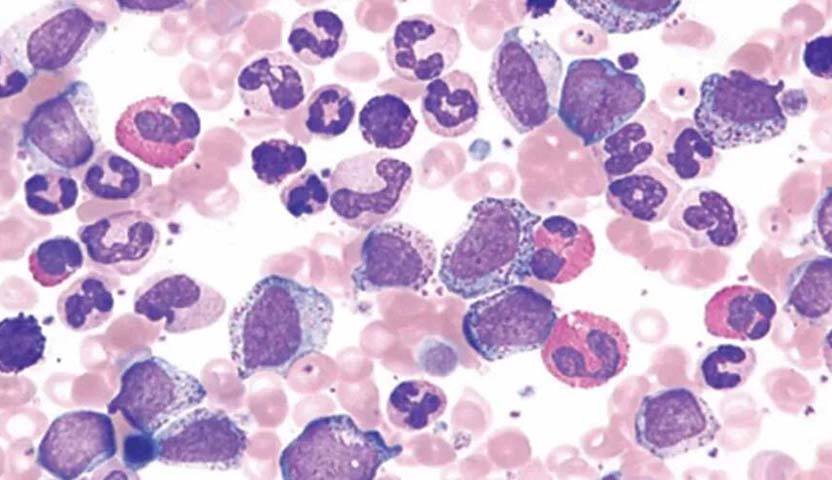

“هل يعود سرطان الدم بعد الشفاء؟” الإجابة هي نعم، من الممكن أن يعود سرطان الدم بعد الشفاء منه، وتسمى هذه الحالة بالانتكاسة، وهي عادة ما تحدث في سرطان الدم إذا وجد الطبيب في التحاليل والفحوصات أن خلايا سرطان الدم عادت وارتفعت مرة أخرى في نخاع العظم، أو إذا كان في دم المريض عدد أقل من الخلايا السليمة.

- تعداد خلايا الدم: الأشخاص المصابين بسرطان الدم لديهم مستويات عالية من بعض أنواع خلايا الدم والخلايا غير الناضجة، لذا إذا ارتفعت هذه القراءات في إحدى التحاليل الطبية، فإن هذا يؤدي إلى زيادة خطر الانتكاسة.

كذلك يمكن التنبؤ بإمكانية الإصابة بالمرض مرة أخرى من خلال بعض الفحوصات الهامة، والتي تساعد الاطباء فحص الدم ونخاع العظام، بذلك نكون قد أجبنا على سؤال هل يمكن التنبؤ بهذا المرض، وسؤال هل يعود سرطان الدم بعد الشفاء.